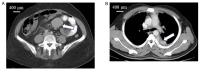

(A) CECT illustrating a mesenteric mass (patient no 4) (arrow). (B) CECT illustrating a posterior mediastinal mass (patient no 6) (arrow).